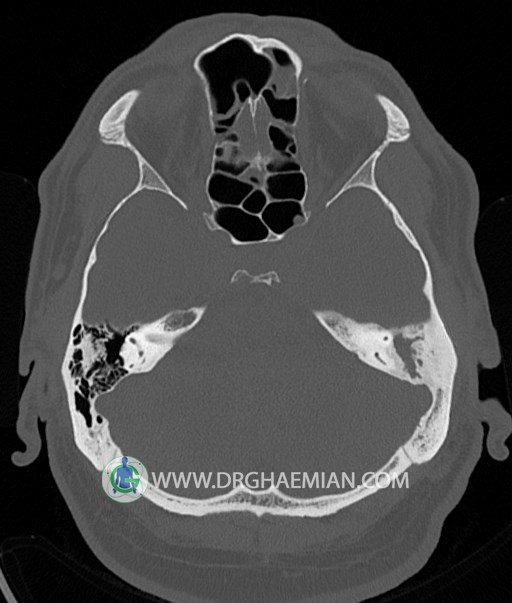

سی تی اسکن گوش داخلی به رادیولوژیست اجازه می دهد تا سطوح مختلف، یا اسلایس هایی از استخوان های که از جمجه به گوش می روند را از طریق امواج ایکس چرخشی مشاهده کند. در این کیس اودیت مدیا، ماستوئیدیت مزمن، اوتیت خارجی، انحراف سپتوم بینی، کونکا بولوزا و افزایش ضخامت سینوس ها مشاهده می شود.

گزارش پزشک :

در HRCT از استخوان تمپورال با مقاطع آگزيال ، ساژيتال و کرونال ظريف ( 0.6 mm ) :

– اپاسيتي گوش مياني چپ ناشي از وجود دانسيته نسج نرمي دراطراف استخوانچه ها همراه با اروژن اسکوتوم و

استخوانچه ها بدون جابجايي در رديف استخوانچه ها مشهود است که مطرح کننده اوتيت مديا همراه با نشانه

هاي مشکوک به کولستئاتوم مي باشد .

– اپاسيتي و اسکلروزيس ماستوئيد چپ نشانه ماستوئيديت مزمن

– اپاسيتي کانال گوش خارجي ناشي از دانسيتي نسج نرمي مطرح کننده external otitis